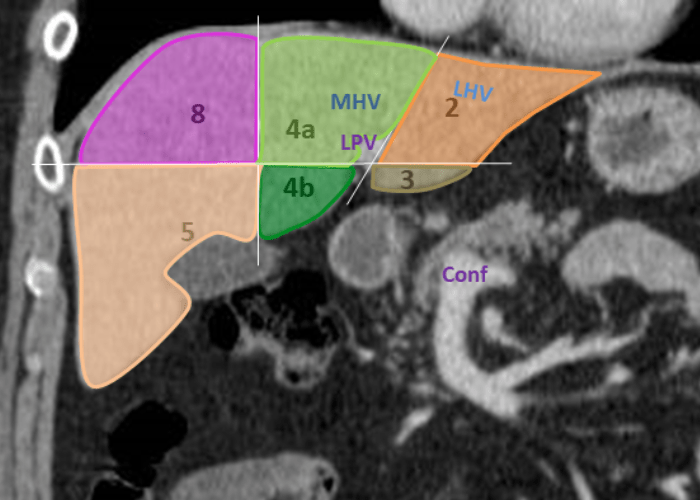

Ct Anatomy Of Liver . The portal and hepatic veins divide the liver into segmental anatomy that allows radiologists and surgeons to be very specific. The anatomy of the liver can be described using two different aspects: Morphological anatomy and functional anatomy. Assessment of vascular and biliary anatomy and presence of anatomic variants may be important for interventional or surgical planning. The traditional morphological anatomy is based on the. Annotated axial ct with contrast of hepatic segmentation and veins 3 articles feature images from this case couinaud classification of. Maximum intensity projection image of ct of upper abdomen demonstrates confluence of superior mesenteric vein ( single arrowhead ) and splenic vein (. Traditionally, the liver was divided into four anatomical lobes: The right, left, caudate and quadrate lobes.

The Radiology Assistant Liver Segmental anatomy Ct Anatomy Of Liver Assessment of vascular and biliary anatomy and presence of anatomic variants may be important for interventional or surgical planning. Morphological anatomy and functional anatomy. The portal and hepatic veins divide the liver into segmental anatomy that allows radiologists and surgeons to be very specific. The right, left, caudate and quadrate lobes. Maximum intensity projection image of ct of upper abdomen. Ct Anatomy Of Liver.